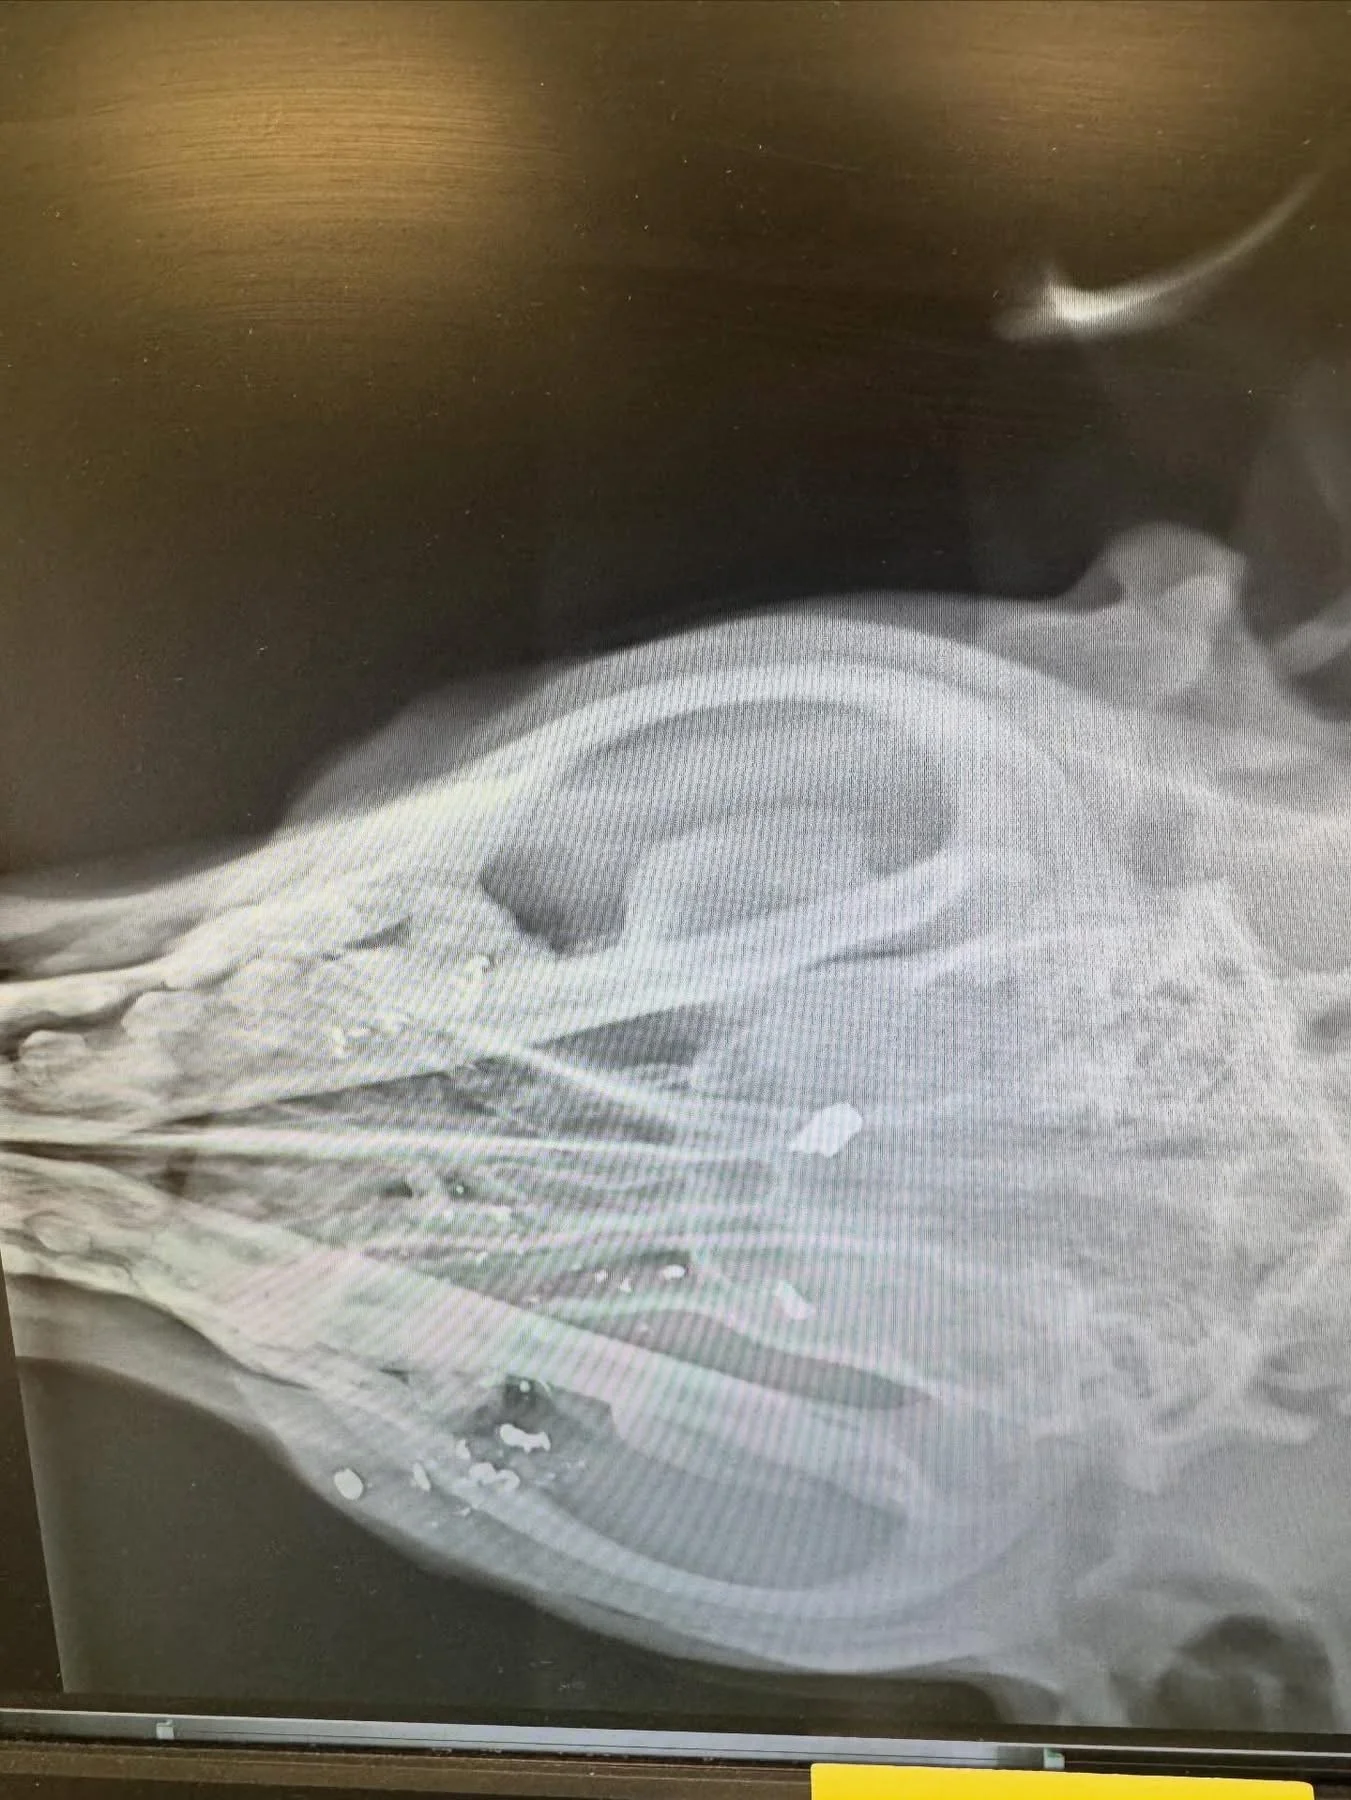

We finally got her safely into my car and dropped her off at the vet. The bullet had gone right through her cheek, tongue, and into her brain. Unfortunately, there’s not much we can do except strong pain medication, antibiotics, and hope 🙏 for a positive outcome.